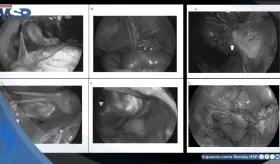

El procedimiento es esencial para diagnósticos complejos, ya que permite analizar directamente el tejido del corazón, siendo clave no solo en el monitoreo de trasplantes, sino también en enfermedades infecciosas y cardiopatías infiltrativas.